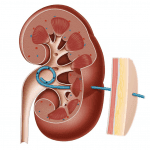

Dẫn Lưu Bể Thận | Bài giảng CĐHA *

Dẫn lưu bể thận qua da (Percutaneous nephrostomy) là một kỹ thuật can thiệp được sử dụng phổ biến trong việc giảm áp hệ thống đường bài xuất thận. Kỹ thuật này được Goodwin và cộng sự lần đầu tiên giới thiệu vào năm 1955. Cho đến nay, dẫn lưu bể thận qua da được phát triển với nhiều cải tiến kỹ thuật khác nhau, cho phép thực hiện an toàn và hiệu quả, được áp dụng phổ biến trong lâm sàng, giúp ngăn ngừa các biến chứng có thể xảy ra do tình trạng tắc nghẽn đường bài xuất cao hệ tiết niệu. Dẫn lưu bể thận qua da thường được coi như là một lựa chọn tạm thời, trước khi thực hiện các biện pháp giải quyết nguyên nhân gây tắc nghẽn…